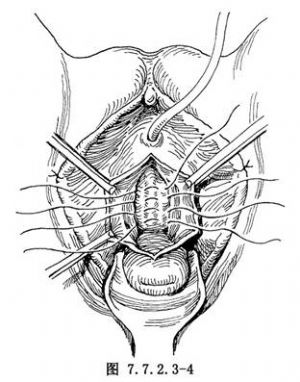

3.折叠尿道 认清尿道和膀胱位置,用丝线于尿道后壁两旁做横行折叠缝合,近侧的缝线应位于膀胱颈,共4针(图7.7.2.3-4)。然后逐一打结,以收紧其后壁。